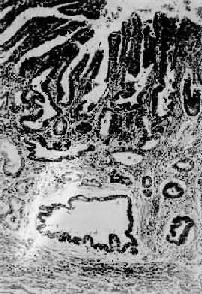

图10-16 弥漫浸润型胃癌 胃壁因癌组织的弥漫浸润而显著增厚 进展期胃癌的肉眼分型常用的还有Borrmann(B)分型。其中B1型为隆起型,B2型为限局溃疡型,B3型为浸润溃疡型,B4型为弥漫浸润型。 镜下,根据癌的组织结构,一般将进展期胃癌分为4种组织学类型: 1.腺癌(adenocarcinoma)最多见,癌细胞大多呈柱状,排列成腺腔(腺管状腺癌,glandular form)(图10-17),腺腔内出现许多乳头(乳头状腺癌,papillary form)。有的癌细胞呈立方形或圆形,由数个癌细胞形成小腺泡(腺泡状腺癌,acinar form)。此型癌组织分化较高,恶性度较低,转移较晚。

图10-17 胃腺癌 癌组织呈腺样结构,弥漫浸润于胃壁内 2.髓样癌(medullary carcinoma)癌细胞无腺样排列,细胞大而多形,异型性显著,恶性度较高,常较早地向深层浸润。 3.硬癌(scirrhous carcinoma)癌细胞较小,圆形或短梭形,呈条索状排列,多无腺管样结构,间质为大量纤维组织(图10-18)。本型恶性度较高。